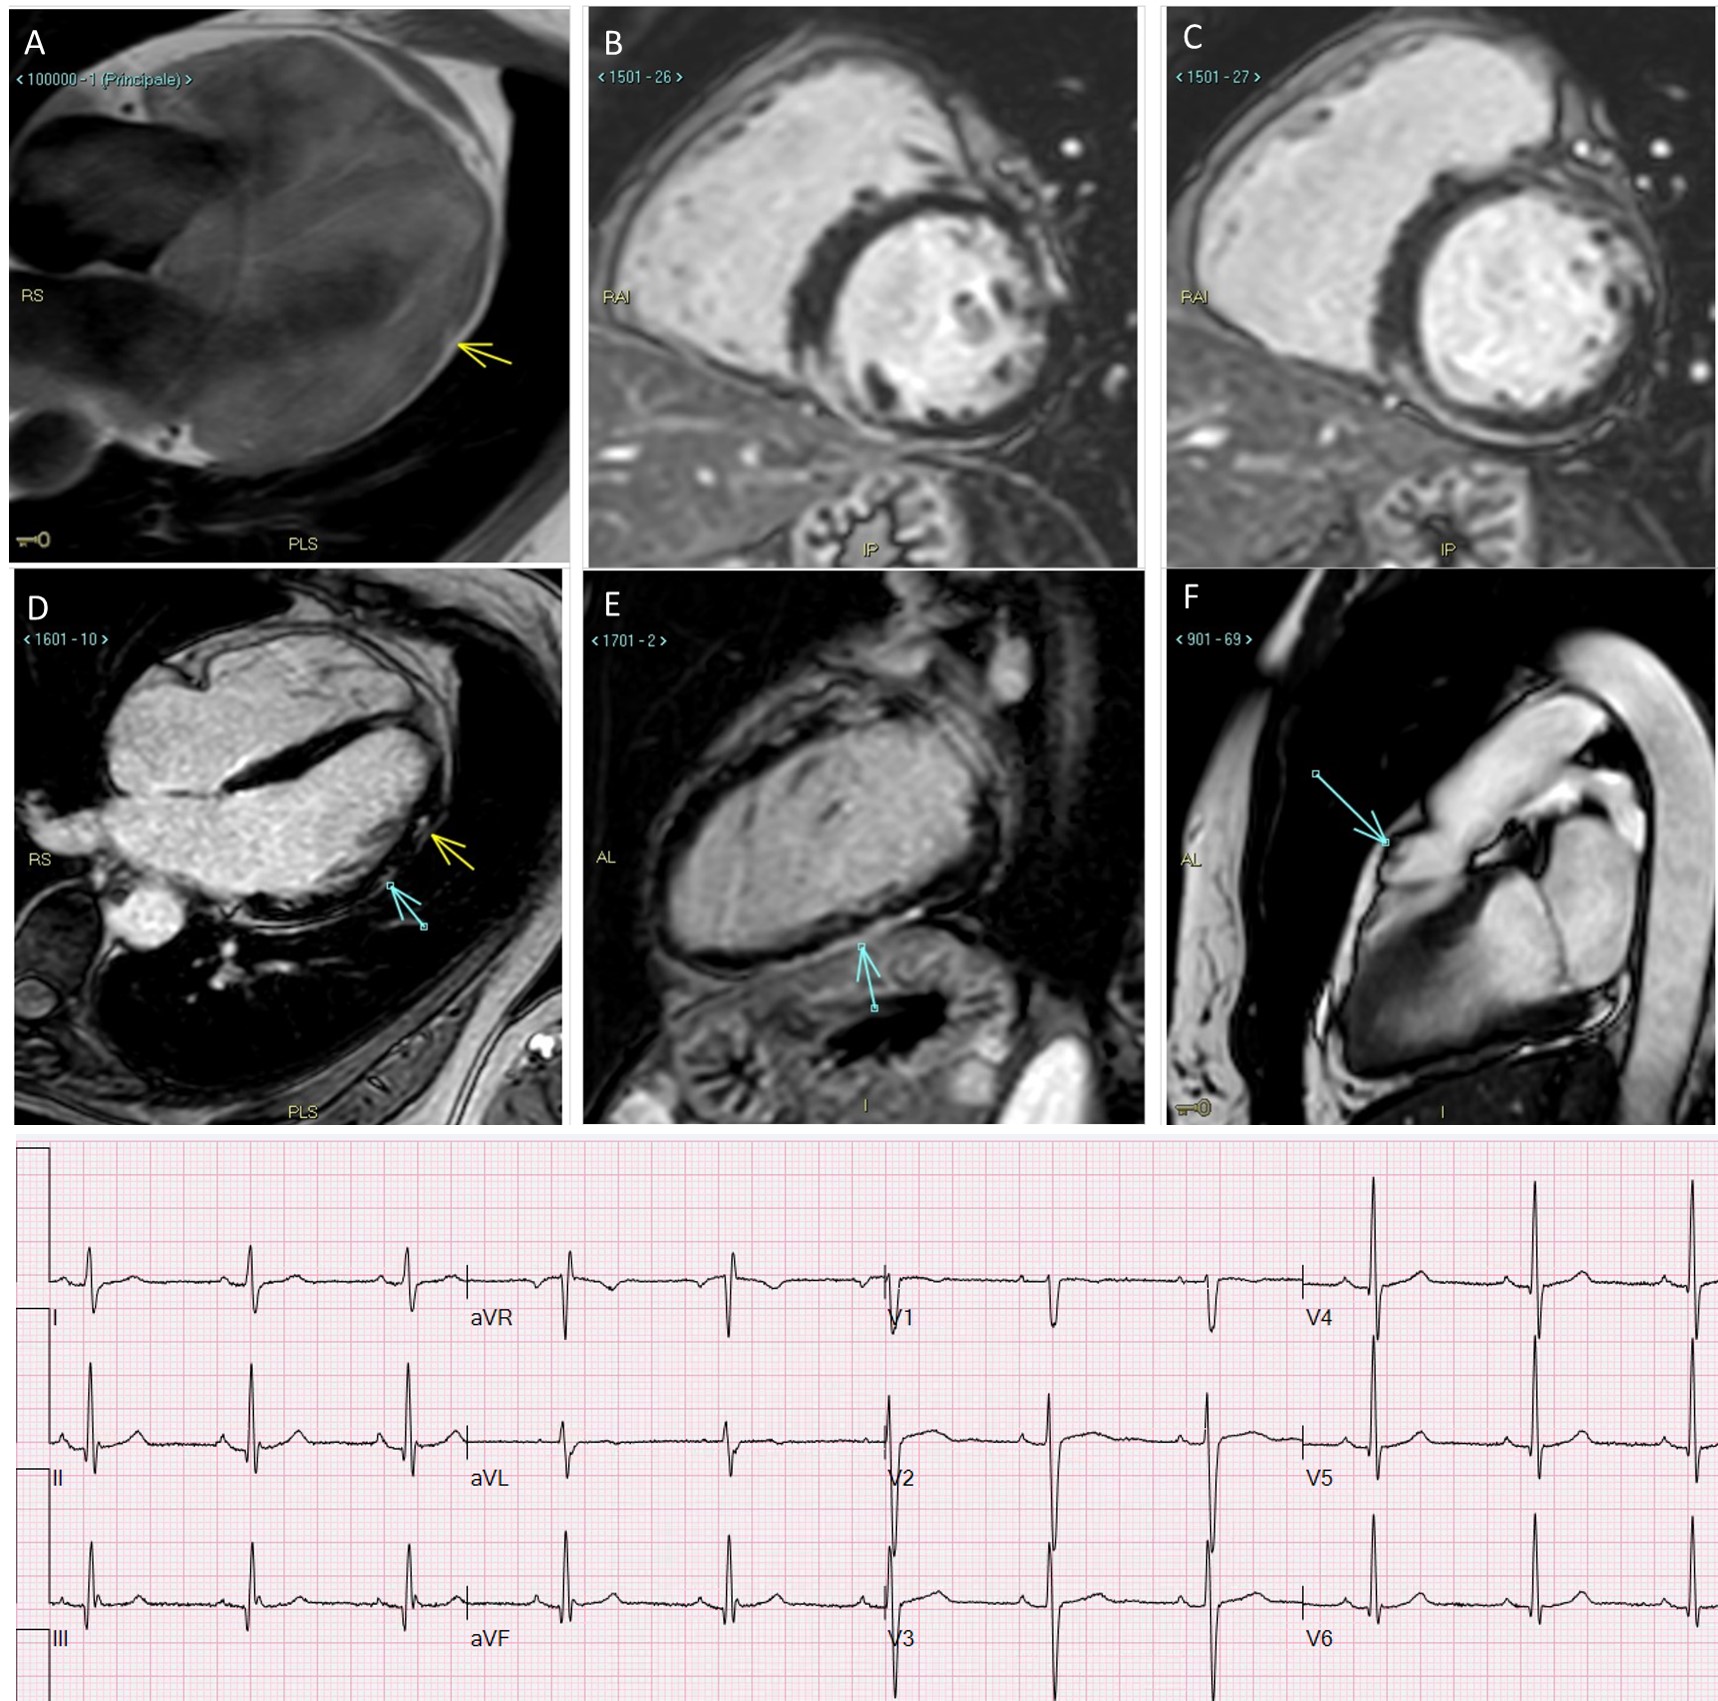

Fig. 1.Late-onset biventricular ACM in a 54-years old lady with self-terminating syncopal ventricular tachycardia, screened at 44 as mother of an ALVC proband, both with desmoplakin mutation. While ECHO and ECG were normal at 44, CMR at 54 shows: (A) fibrofatty infiltration located in subepicardic lateral wall of the LV. (B,C) Ring-like LGE located in the inferior wall and in the inferior interventricular septum. (D) Lateral wall focal areas of LGE and mild RV enlargement with anterior hypokinesia. (E) Inferior wall LGE. (F) RVOT bulging. See fragmented QRS mimicking a pseudo-epsilon wave in inferior limbs (negative in aVL) at ECG.